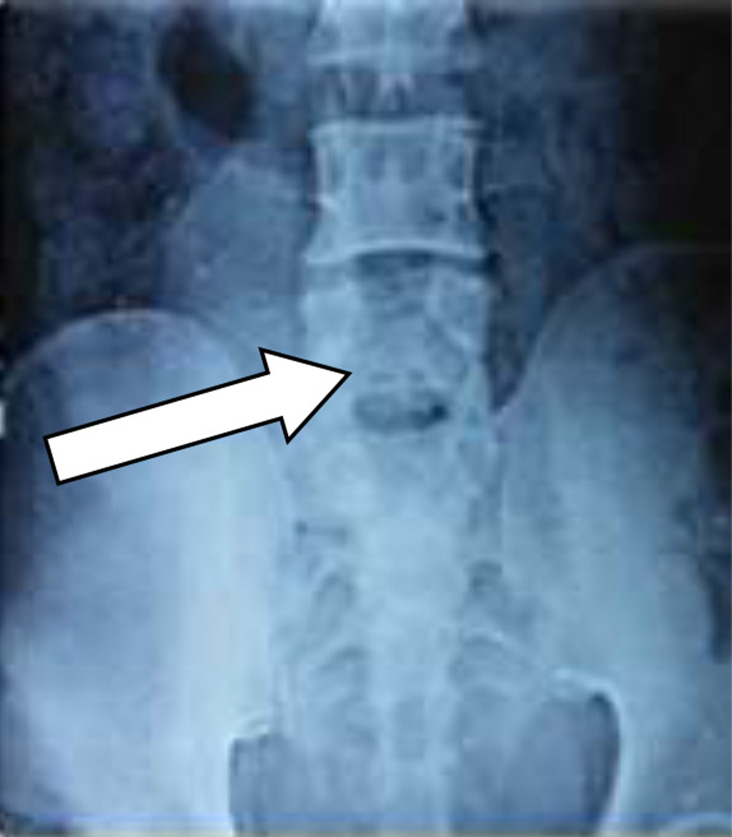

Following spinal anesthesia, patients were positioned prone. A midline incision was made one level above and below the involved segment. C-arm intensifier was utilized, especially when sacralization or lumbarization was identified in preoperative imaging. The spine and laminae were exposed, centering on the affected disc space. Portions of the spinous process and interspinous ligament were excised. The lower halves of both laminae were removed until the epidural fat became visible through the ligamentum flavum in the midline. (Fig. 1). The ligamentum flavum was excised bilaterally, and in certain cases, the overhanging portions of the hypertrophied medial facets were removed using a Kerrison punch. A standard technique was employed for discectomy, ensuring the complete removal of all visible disc material. Both nerve roots were examined for any additional compressive elements before they entered their respective foramina. For L5-S1 disc prolapse, only ligamentum flavectomy was performed with limited laminectomy (even less than the lower half) to facilitate adequate discectomy. The wounds were closed in layers after achieving proper hemostasis. For illustration images from a case of L5-S1 disc prolapsed are presented(pre-operative MRI and post operative X-ray) (Fig. 2-4).

Fig. 4. X-ray of the LS spine (anteroposterior (A) and lateral (B) views) done postoperatively demonstrating the post laminectomy defects(indicated by arrows)